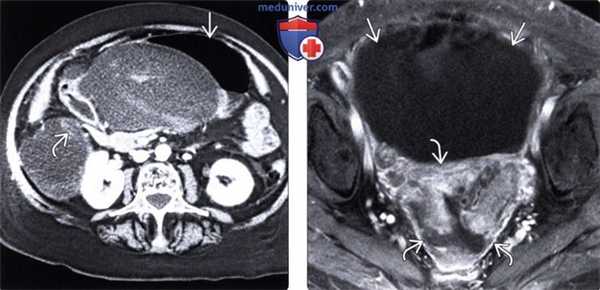

(Слева) На аксиальной КТ с контрастом определяются отграниченные скопления жидкости со сложной структурой, являющиеся результатом желчного перитонита из-за повреждения билиарного тракта. Визуализируется жидкость в малом брюшинном мешке, которая смещает желудок и двенадцатиперстную кишку обычно жидкость здесь скапливается в результате других причин (панкреатит, язва желудка), перитонита, канцероматоза.

(Справа) На аксиальной Т1 МР томограмме с жироподавлением и контрастным усилением определяется отграниченный асцит BE в полости таза. Обратите внимание на выраженное утолщение брюшины и повышенное накопление контраста (больше в задних отделах) при канцероматозе брюшины.